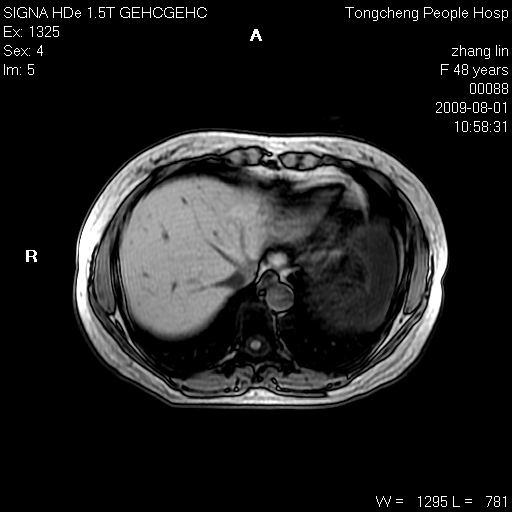

女,48岁。健康体检,彩超发现右肾占位性病变。平素健康。

临床诊断:右肾占位性病变,性质待定(囊肿?肿瘤?)。

上中腹部mr平扫+增强扫描,图像如下:

右肾上极见一类圆形病灶,t1wi呈等信号t2wi呈等高混杂信号,三期增强无强化,边界清---考虑囊肿出血。

同反相位均表现为等信号,病变无强化,考虑含蛋白的囊肿可能,弥散加权相或许有些帮助,